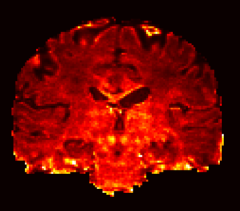

Figure 7 shows the MSE calculated between the normalized diffusion signal and the estimated diffusion signal of NODDI and NODDI-SH. It is worth to mention that in this picture we use a very narrow range of values in order to emphasize the contrast and that both techniques were able to estimate the diffusion signal accurately. NODDI MSE appears to be higher in white matter, and in particular in single fiber areas, with respect to gray matter or CSF where it is close to zero. NODDI-SH MSE presents a more uniform pattern in the white matter, gray matter, and CSF. The highest MSE values for NODDI-SH were found in the corpus callosum and in the basal nuclei.

| NODDI MSE | NODDI-SH MSE |

|---|---|

![]() |